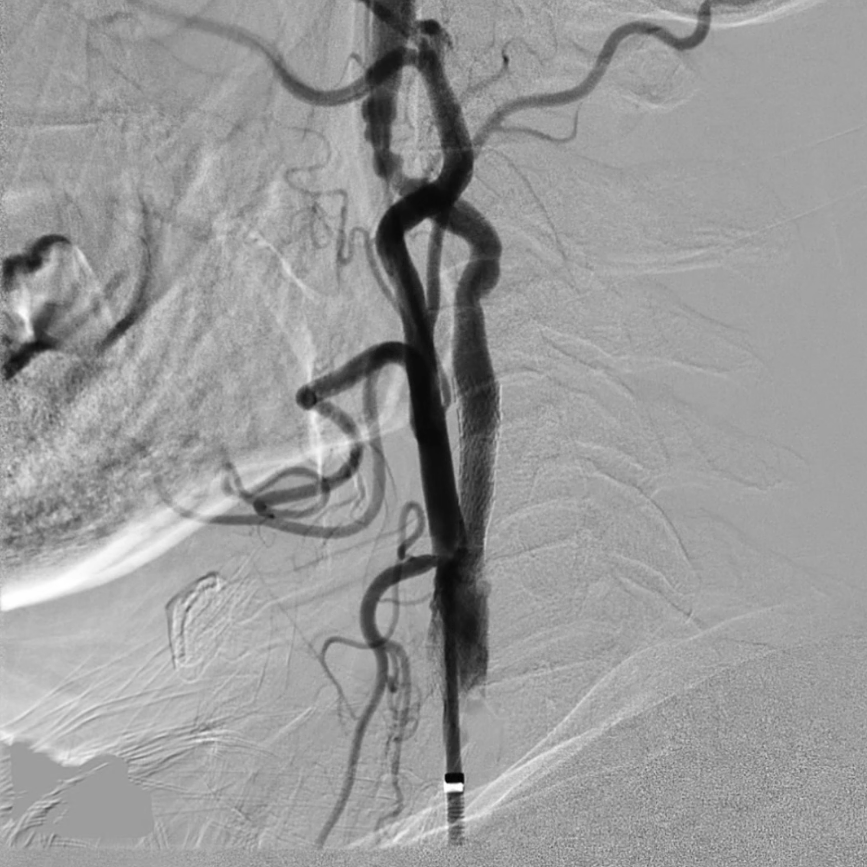

预扩张与支架植入:匹配病变特点的器械选择

预扩张:使用5/30mmAviator球囊,扩张前需将患者心率提升至80次/分以上(避免扩张时迷走神经反射导致心率骤降);

支架选择:选用8/40mmPRECISE开环支架,其柔顺性好,适合迂曲的颈动脉解剖结构,定位精准且完全覆盖病变。

造影显示:支架膨胀良好,无需后扩张;

颅内血供:左侧颈内动脉血流通畅,因右侧闭塞,左侧成为全脑主要供血通路,血供恢复满意